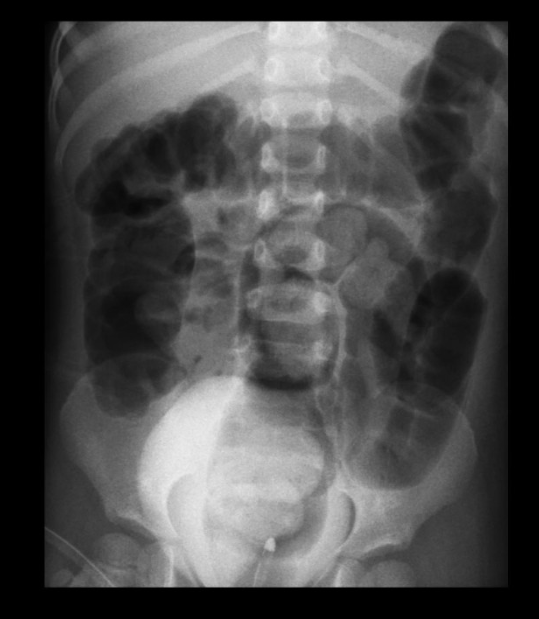

해부학적 특징은 영아기 장폐색의 주요 원인 중의 하나로서 흔히 위쪽창자가 아래창자 속으로 말려들어 가는 것을 말한다. 돌막창자가 큰창자 안으로 밀려 들어 가는 것이 95% 정도로서 가장 흔하다. 환아의 80%가 1년 미만의 영아인데, 이 중 5~11개월 사이의 호발연령이고, 여아보다 남아에게서 3배 정도 더 많다. 일반적으로 창자겹침증의 원인은 밝혀지지 않았다. 생리적 특징은 심한 복통으로 울며 다리를 배위로 끌어당이고 이때 구토를 동반한다. 발작후에 5~15분간의 무증상 시기가 있으며 이를 반복한다. 증상 발현 후 초기 몇 시간 동안은 정상적인 대변이 나올 수 있으나 그 후에 대변 및 방귀 배출은 거의 없다. 발병 12시간 이내 특징적인 혈액이 혼합된 대변을 환자의 60%에서 관찰할 수 있다. 조영제는 황산바륨 1통과 warm saline 1병(1000mL)을 준비한다. 미세한 병변을 진단하는 것이 아니고 폐색 부위의 관찰과 장충첩을 푸는 것이 목적이므로 고농도 황산바륨을 사용할 필요가 없다. 음성조영제로는 공기가 있다. 준비물품은 바륨통(enema can), enema tip 또는 foley catheter, 수술용 장갑, 젤리, 공기펌프(공기 정복술시 이용), 압력계, stand 폴대(I.V. stand) 등이 필요하다.

검사법에 바륨정복술(barium reduction)은 수술요법에 비해 손상이 적고 마취의 위험성이 없이 비교적 간단히 중복된 장을 푸는 방법으로 시술 후 합병증이 적고 입원이 불필요하여 환자에게 경제적 부담을 줄 일 수 있다. 그러나 무리하게 시행하면 장이 파열될 가능성이 있고 이로 인해 복막염이 발생하게 되며 방사선피폭도 문제가 될 수 있다. 공기정복술(air reduction)은 공기를 이용해 장중적을 해소시키는 방법으로 진단측면에서 바륨정복술에 비해 절차가 간단하고 교정시간도 짧으며 장천공(창자뚫림) 위험도 상대적으로 낮아 바륨에 의한 복막염이 생기지 않으므로 천공에 의한 부작용이 훨씬 경미하다. 그러나 초보자의 경우 장중첩의 진단과 교정과정의 추적관찰이 어려운 단점이 있다. 주의사항은 3.3.3법칙을 준수한다.(3세 이하의 어린이에게 1회 교정시간을 3분 이내로 한정하여 3회까지 시행한다) 만일 장중첩이 풀리지 않으면 진경제(meperidine hydrochoride: 2mg)을 투여하고 10분 후에 시행하며 그래도 교정되지 않으면 포기하고 수술적 방법으로 대치하여야 한다. 바륨이나 공기정복술은 수술에 비해 장의 손상이 적다. 시술 후 합병증이 적으며 입원을 할 필요가 없다. 공기정복술은 바륨정복술보다 간단하고 교정시간이 빠르다. 장천공시 부작용이 적어서 현제는 공기정복술을 많이 하고 있다.